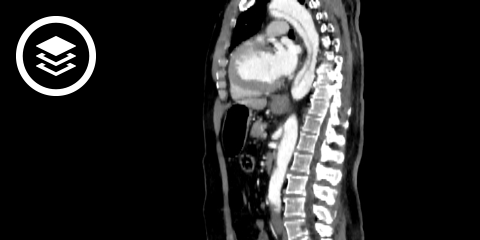

CT-Fallbeispiel

DICOM-Modelle können auf Mobilgeräten leider nicht angezeigt werden.

Bildquelle

- Bildquelle DICOM-Viewer: Datensatz freundlicherweise zur Verfügung gestellt durch die Klinik für diagnostische und interventionelle Radiologie, St. Vinzenz Hospital Köln